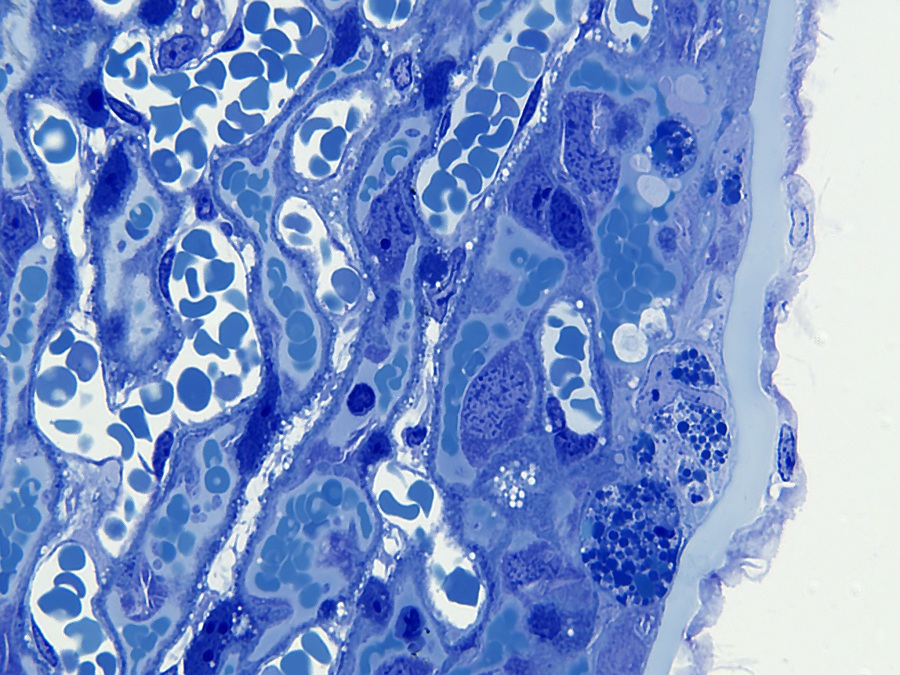

De decidua wordt van de embryonale labyrintische zone gescheiden door de junctionele zone. De junctionele zone bevat maternale bloedvaten (veneuze drainage), trofoblastreuscellen en spongiotrofoblastcellen. Trofoblastcellen zijn over het algemeen erg groot met bizar gevormde of meervoudige kernen. Reusceltrofoblasten zijn, zoals hun naam al zegt, erg groot - tot 100 µm in diameter en bevinden zich het dichtst bij de decidua. Spongiotrofoblasten zijn fagocytisch[6] en kunnen gefagocytiseerde erytrocyten bevatten en bevinden zich dichter bij de labyrintische zone. De labyrintische zone bestaat uit nauw tegenover elkaar liggende foetale en maternale bloedkanalen. De foetale bloedkanalen zijn bekleed met dunne endotheelcellen en bevatten grote onrijpe gekerfde rode bloedcellen, terwijl de maternale bloedkanalen bekleed zijn met grote labyrintische trofoblastcellen.

Reusceltrofoblastcellen[3] zijn betrokken bij de modulatie van de maternale vasculatuur van de decidua en ze produceren verschillende placenta-specifieke hormonen die lijken op het hypofysehormoon prolactine[6]. Dit zijn onder andere Pl-1, Pl-2 (placentalactogeen) en proliferine, die uitsluitend door reuscellen worden uitgescheiden. Pl-1 en Pl-2 moduleren de activiteit van de eierstokken door de productie van luteaal progesteron te stimuleren, wat essentieel is voor het behoud van de zwangerschap. Bovendien zijn Pl-1 en Pl-2 betrokken bij de controle van de borstklierontwikkeling.